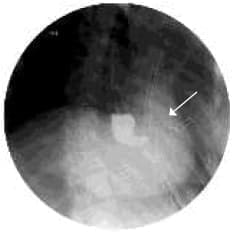

Al segundo día postquirúrgico presenta salida de material alimentario por las sondas de tórax, lo que establece presunción diagnóstica de fístula gastro-pleural, que luego se documenta por endoscopía (Figuras 1 y 2), tomografía computarizada (Figura 3) y estudio contrastado de vías digestivas altas (Figura 4).

Figura 4. Se observa el medio de contraste pasando a la pleura a través de la fistula. |